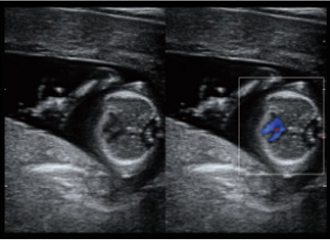

临床图像